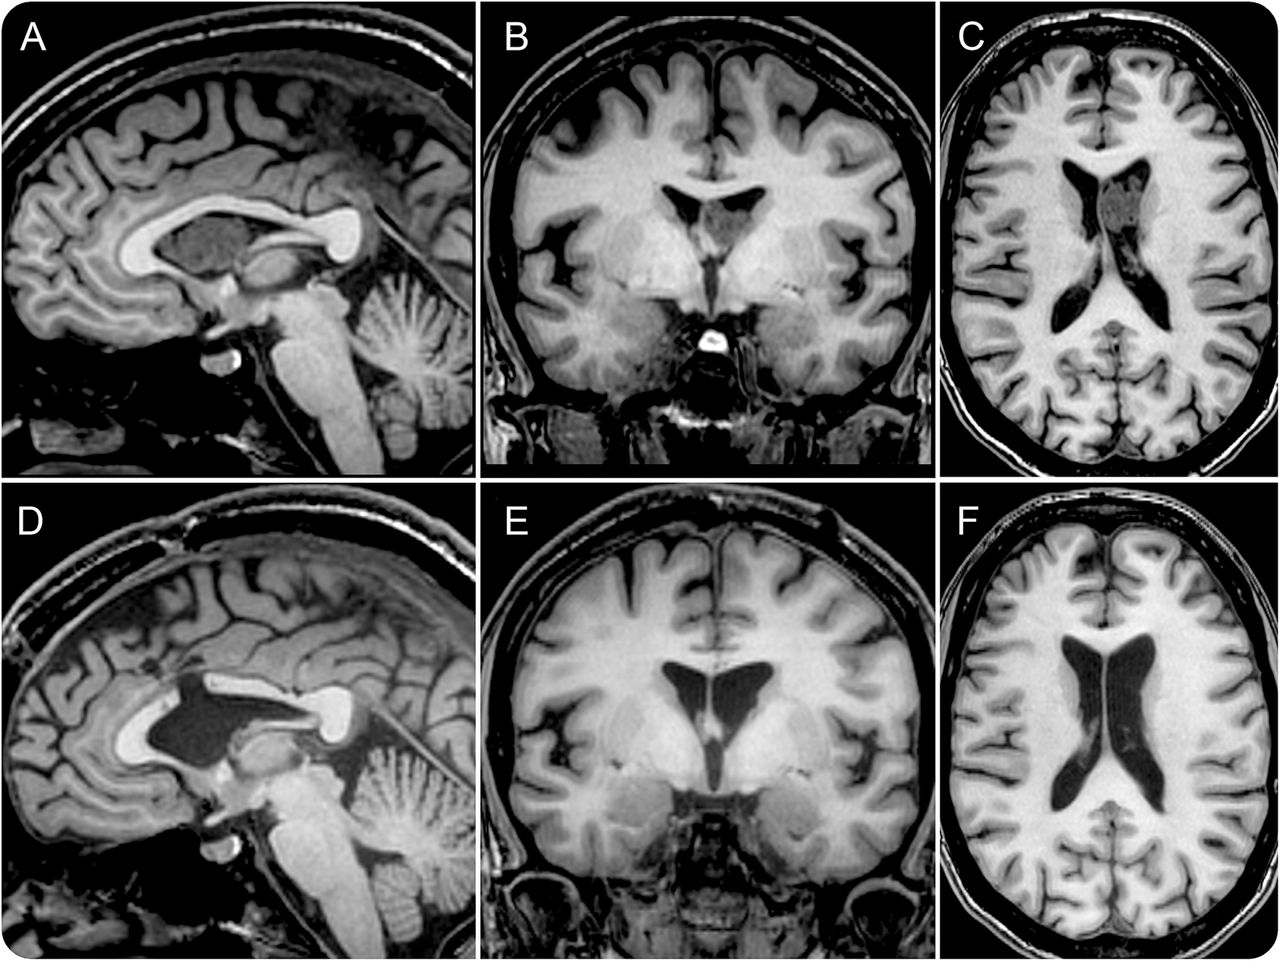

图

脑室肿瘤导致间歇性脑积水

MRI显示脑室质量(A)和孟氏孔部分梗阻(B)导致轻微的左侧侧脑室扩大(C),咳嗽转移肿瘤,完全自由流动的阻塞脑脊液孟氏孔,造成间歇性脑积水。孟氏孔阻塞手术切除后消失subependymoma (D-F)。